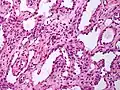

High power view showing a vascular tumor with cuboidal endothelium lining the vessels. Few entrapped seminiferous tubules are also noted (arrow). Characteristic budding, hobnail-like endothelial cells visible.

Characteristic budding, hobnail-like endothelial cells visible.